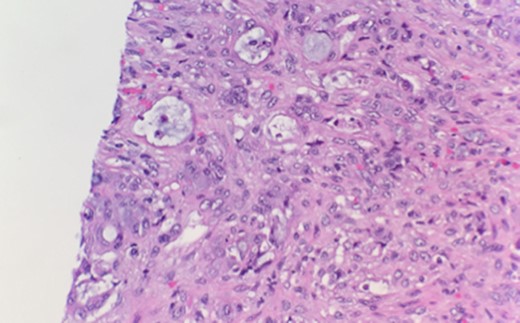

High-power examination reveals some malignant cells demonstrating Signet ring cell features (Fig. 2).

High-power examination reveals some malignant cells demonstrating Signet ring cell features.